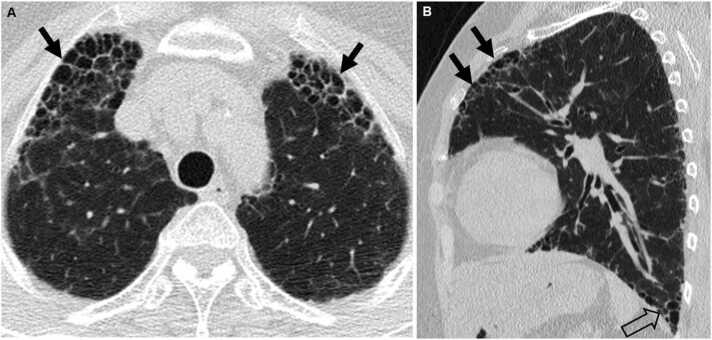

Connective tissue diseases (CTDs) demonstrating features of interstitial lung disease (ILD) include systemic lupus erythematosus (SLE), rheumatoid arthritis (RA), systemic sclerosis (SSc), dermatomyositis (DM) and polymyositis (PM), ankylosing spondylitis (AS), Sjogren syndrome (SS), and mixed connective tissue disease (MCTD). On histopathology of lung biopsy in CTD-related ILDs (CTD-ILDs), multi-compartment involvement is an important clue, and when present, should bring CTD to the top of the list of etiologic differential diagnoses. Diverse histologic patterns including nonspecific interstitial pneumonia (NSIP), usual interstitial pneumonia (UIP), organizing pneumonia, apical fibrosis, diffuse alveolar damage, and lymphoid interstitial pneumonia can be seen on histology in patients with CTD-ILDs. Although proportions of ILDs vary, the NSIP pattern accounts for a large proportion, especially in SSc, DM and/or PM and MCTD, followed by the UIP pattern. In RA patients, interstitial lung abnormality (ILA) is reported to occur in approximately 20-60% of individuals of which 35-45% will have progression of the CT abnormality. Subpleural distribution and greater baseline ILA involvement are risk factors associated with disease progression. Asymptomatic CTD-ILDs or ILA patients with normal lung function and without evidence of disease progression can be followed without treatment. Immunosuppressive or antifibrotic agents for symptomatic and/or fibrosing CTD-ILDs can be used in patients who require treatment.

表现为间质性肺疾病(ILD)特征的结缔组织病(CTD)包括系统性红斑狼疮(SLE)、类风湿关节炎(RA)、系统性硬化症(SSc)、皮肌炎(DM)和多发性肌炎(PM)、强直性脊柱炎(AS)、干燥综合征(SS)以及混合性结缔组织病(MCTD)。在CTD相关ILD(CTD-ILD)的肺活检组织病理学检查中,多部位受累是一个重要线索,若出现这种情况,应将CTD列为病因鉴别诊断的首要考虑。CTD-ILD患者的组织学检查可见多种组织学模式,包括非特异性间质性肺炎(NSIP)、寻常型间质性肺炎(UIP)、机化性肺炎、肺尖纤维化、弥漫性肺泡损伤和淋巴细胞间质性肺炎。尽管ILD的比例各不相同,但NSIP模式占很大比例,尤其是在SSc、DM和/或PM以及MCTD中,其次是UIP模式。据报道,RA患者中约20%-60%会出现间质性肺异常(ILA),其中35%-45%的患者CT异常会进展。胸膜下分布以及基线时ILA受累程度较高是与疾病进展相关的危险因素。无症状的CTD-ILD或ILA且肺功能正常且无疾病进展证据的患者可以不进行治疗而进行随访。有症状的和/或纤维化的CTD-ILD患者若需要治疗,可使用免疫抑制剂或抗纤维化药物。